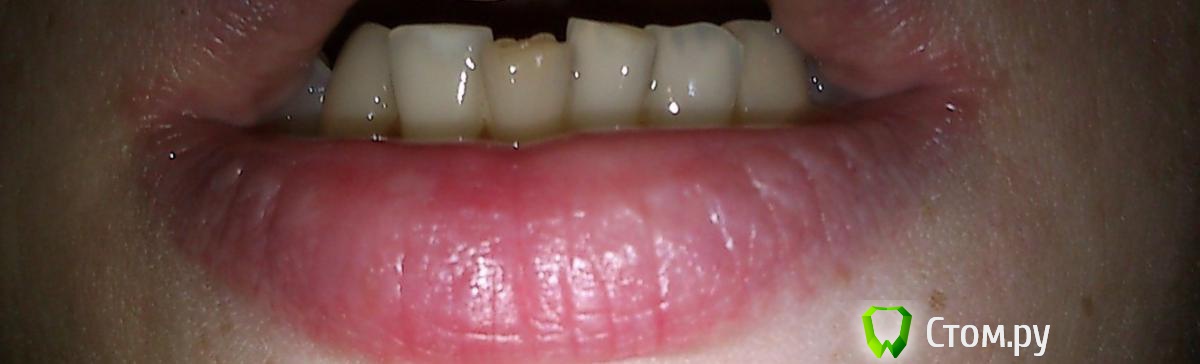

Julia_86 Опубликовано 10 сентября, 2014 Автор Поделиться Опубликовано 10 сентября, 2014 Фото. Ссылка на комментарий

kriokov Опубликовано 10 сентября, 2014 Поделиться Опубликовано 10 сентября, 2014 Надо, чтобы ортодонты посмотрели. Так как может быть вариант и с удалением измененного в цвете зуба. 2 Ссылка на комментарий

Bier Опубликовано 10 сентября, 2014 Поделиться Опубликовано 10 сентября, 2014 скорее всего это мертвый зуб. Терапевтическое лечение возможно. Ну если только ортодонты не скажут удалять, но ассиметричное удаление редкий случай, да и не супер это получится эстетически. 2 Ссылка на комментарий